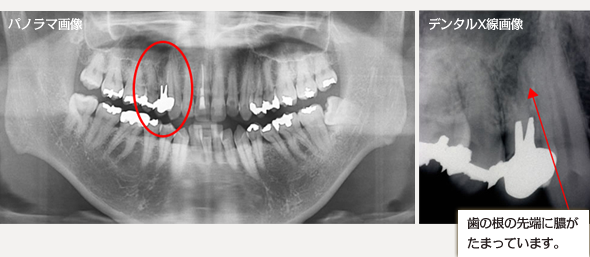

歯の根の病変

CT断層撮影によって、歯をあらゆる角度から見ることができるので、確実な診査・診断ができます。